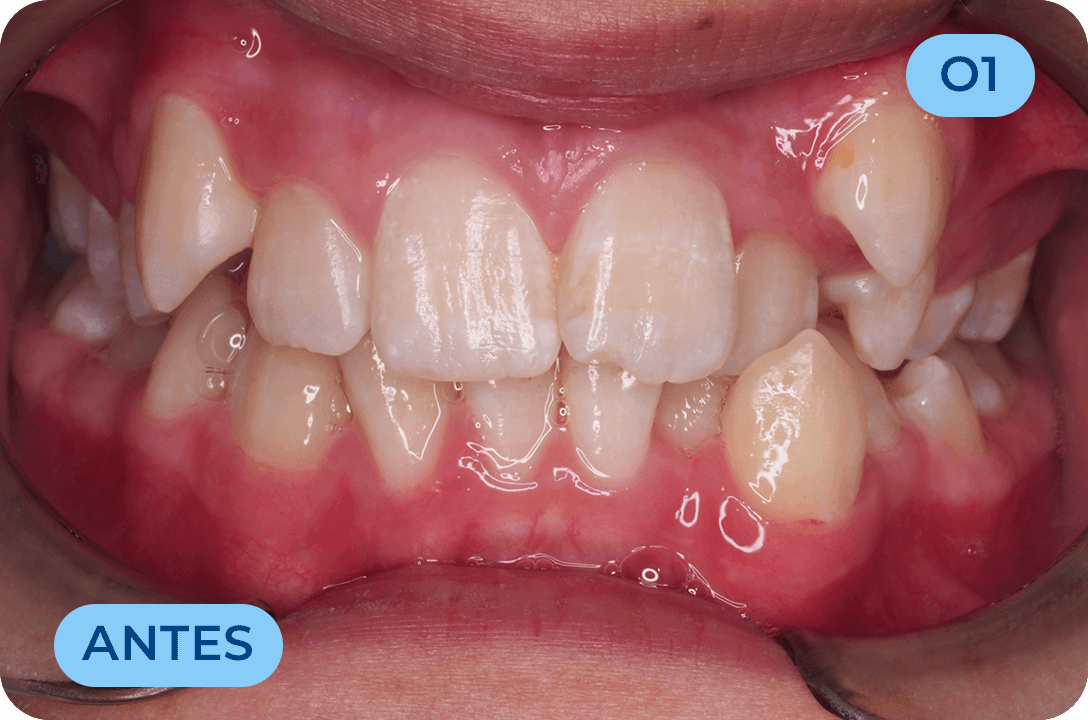

Ortodontia

É a especialidade da Medicina Dentária que se debruça sobre o estudo e correção das más posições dentárias e dos maxilares. Atualmente é possível tratar pacientes de todas as idades, no entanto a 1ª consulta deve ser realizada ainda na infância para intercetar eventuais problemas de desenvolvimento esquelético e funcional.